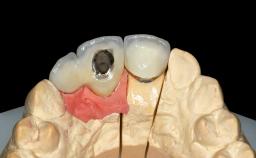

Replacement of Teeth 12 and 13 with Tissue-Level Implants

Prosthesis Type FDP

SAC Level Advanced

Defining Characteristics Up to three missing teeth to be replaced with an implant-borne restoration or restorations

Loading Protocol Conventional or early

Retention Cemented, with prosthesis margin < 3mm submucosal Cemented, with prosthesis margin < 3mm submucosal